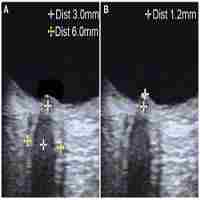

| Abstract | Background: The clinical presentation of cerebral venous sinus thrombosis (CVST) overlaps with that of idiopathic intracranial hypertension (IIH), but no screening tool exists. We investigated the role of eye-neck integrated ultrasound in the diagnosis and differentiation of IIH and CVST. Methods: Twenty IIH patients, 30 CVST patients, and 40 healthy controls were retrospectively analyzed. The ultrasonographic optic nerve sheath diameter (ONSD) and hemodynamic characteristics of the internal jugular veins (IJVs) were recorded. The cerebrospinal fluid opening pressure was measured after ultrasonic examination. Results: The ONSD was significantly larger in IIH patients than in controls (4.71±0.41 vs. 3.93±0.24 mm, p<0.001). The ONSD cut-off for IIH diagnosis was 4.25 mm (AUC=0.978; 95% CI: 0.95-1.0, p<0.001, sensitivity: 90%, specificity: 93%). In the CVST group, 22 (73.3%) patients had elevated intracranial pressure (ICP); the mean ONSD was significantly higher in patients with increased ICP than in those without (4.43±0.33 vs. 3.95±0.17 mm, p<0.001). The mean blood flow volume (BFV) was significantly reduced in CVST patients (425.17±349.83 mL/min) compared to that in controls (680.37±233.03 mL/min, p<0.001) and IIH patients (617.67±282.96 ml/min, p=0.008). The optimal BFV cut-off for predicting CVST was 527.28 ml/min (AUC=0.804, 95% CI: 0.68-0.93, p<0.001, sensitivity: 80%, specificity: 78%). The velocity of the unilateral IJVs-J3 segment decreased or remained constant during deep inspiration (abnormal respiratory modulate blood flow test, ARMT) in 32.5% of controls, with no bilateral ARMT. The prevalence of bilateral ARMT was 25% in IIH patients (2=12.9, p=0.005) and 27% in CVST patients (2=17.6, p=0.001). Conclusion: Eye-neck integrated ultrasound is an easily available bedside technique to assess ICP and hemodynamic characteristics of IJVs. ONSD measurement can identify patients with increased ICP, and reduced IJV BFV may aid the differentiation of CVST and IIH. |